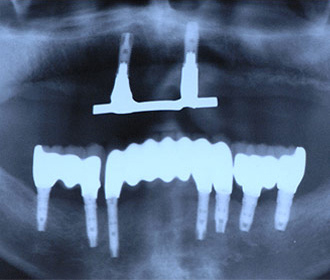

外傷による上顎左右11抜歯後即時インプラント+インビザライン矯正

インプラント治療時にはチタンメッシュ+人工骨による大掛かりな骨移植を行っている。

インプラント治療直後のレントゲン写真。

網目状のものがチタンメッシュ、ピンで骨に固定。 -